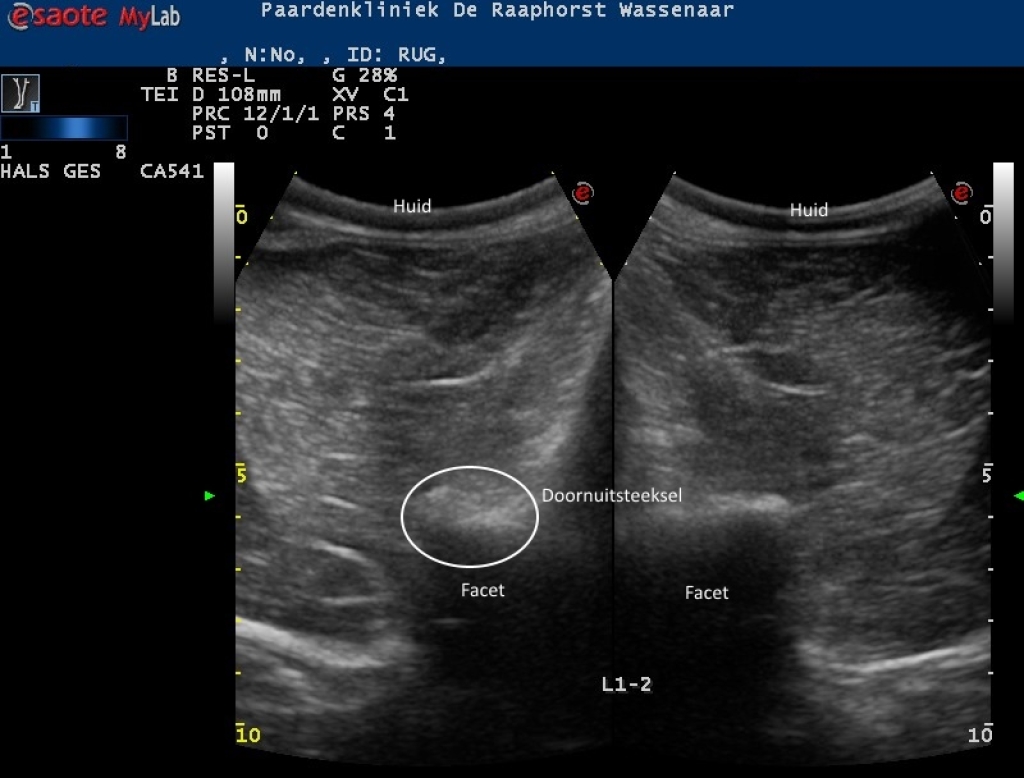

Rechts: Echobeeld van artrose van een facetgewricht in het lendengebied

Echobeeld van artrose van een facetgewricht in het lendengebied